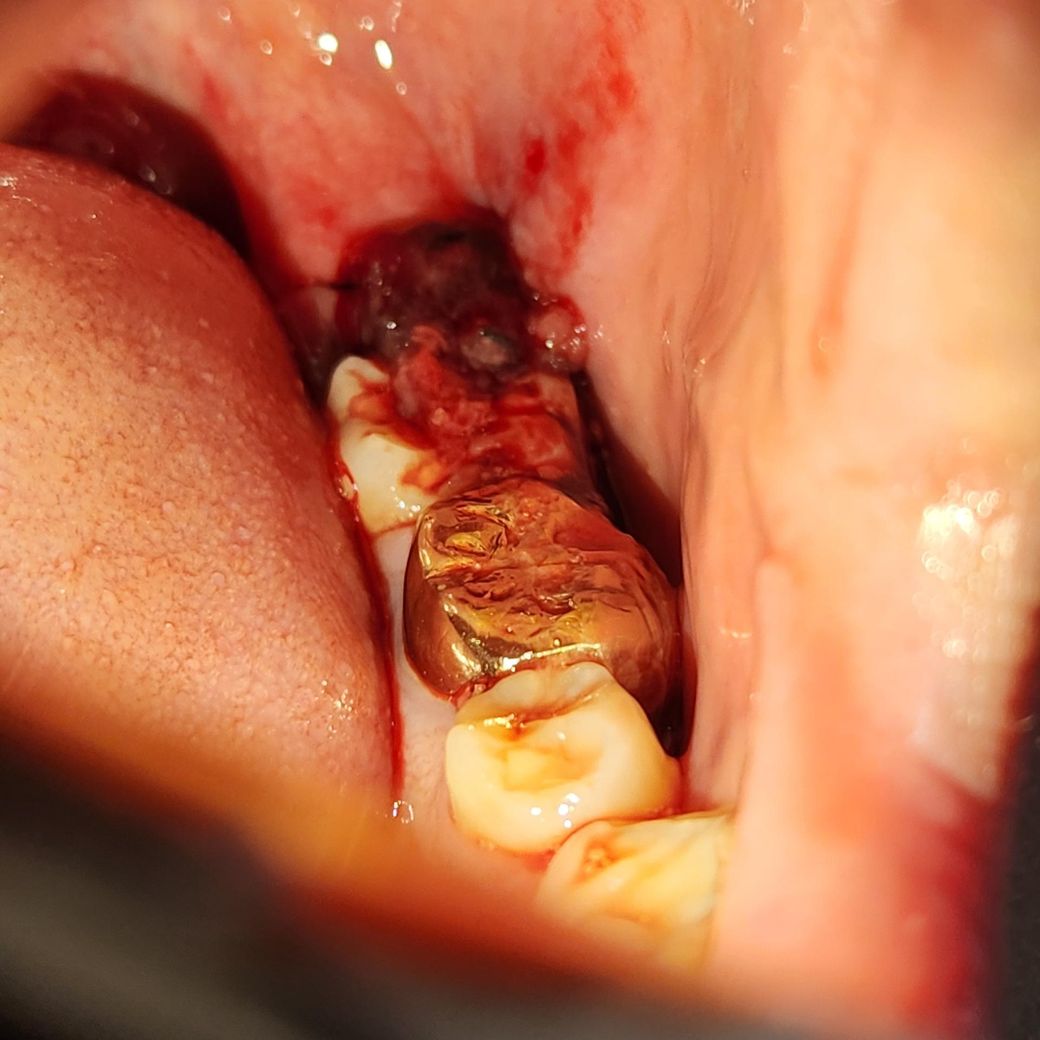

사랑니 발치 후 피가 나는데 확실히 모르겠어요

어제 오후2시에 사랑니를 발치 후 오후7시까지 출혈이 안멈춰서 거즈를 2시간마다 바꾸면서 잤습니다. 근데 오늘 새벽5시에 확인했더니 입 안에 피가 많이 고여있어서 가글을 하고 다시 2시간동안 거즈를 물었습니다. 그랬더니 어느정도 진정된거 같은데 사진을 보시다시피 괜찮은건가요?

그리고 사진 속 맨 끝에 피덩어리로 가려진게 실밥이고, 안보이지만 지렁이 모양으로 피덩어리가 옆에 있습니다. 이것도 원인인가요?

• 1번 째 사진

자극이 될 수 있으므로 과도한 가글은 삼가시고요 바깥으로 삐져나온 혈병(피떡)은 어차피 치유에 큰 의미가 없으니 걷어내셔도 됩니다. 지금으로서는 출혈이 있는 것은 아닌 것 같습니다.